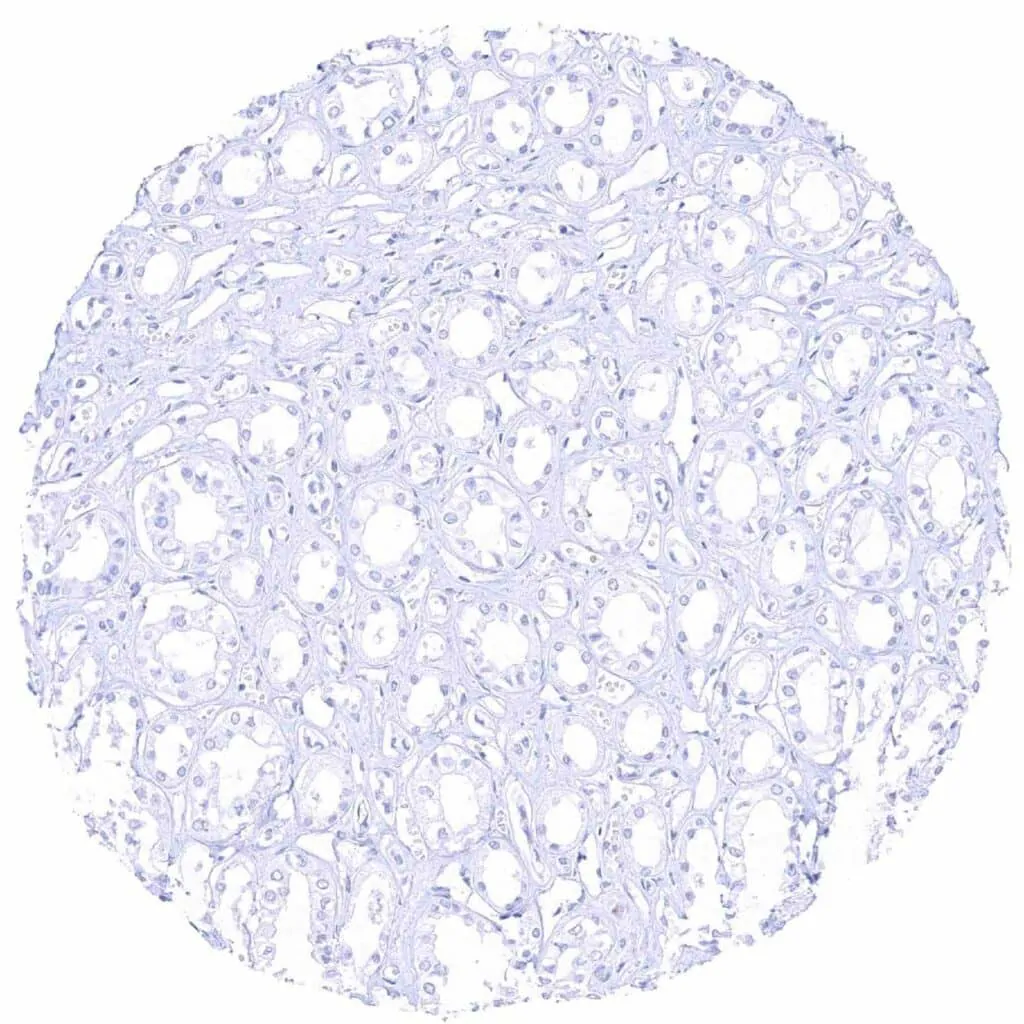

Testis